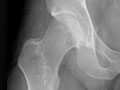

Extremity X-Ray

An extremity X-ray is a picture of your hand, wrist, arm, foot, ankle, knee, hip, or leg. It is done to see whether a bone has been fractured or a joint dislocated. It is also used to check for an injury or damage from conditions such as an infection, arthritis, bone growths (tumors), or other bone diseases, such as osteoporosis.

• Find changes in your bones caused by conditions such as an infection, arthritis, bone growths (tumors), osteoarthritis of the hip, osteoarthritis of the knee, or other bone diseases.